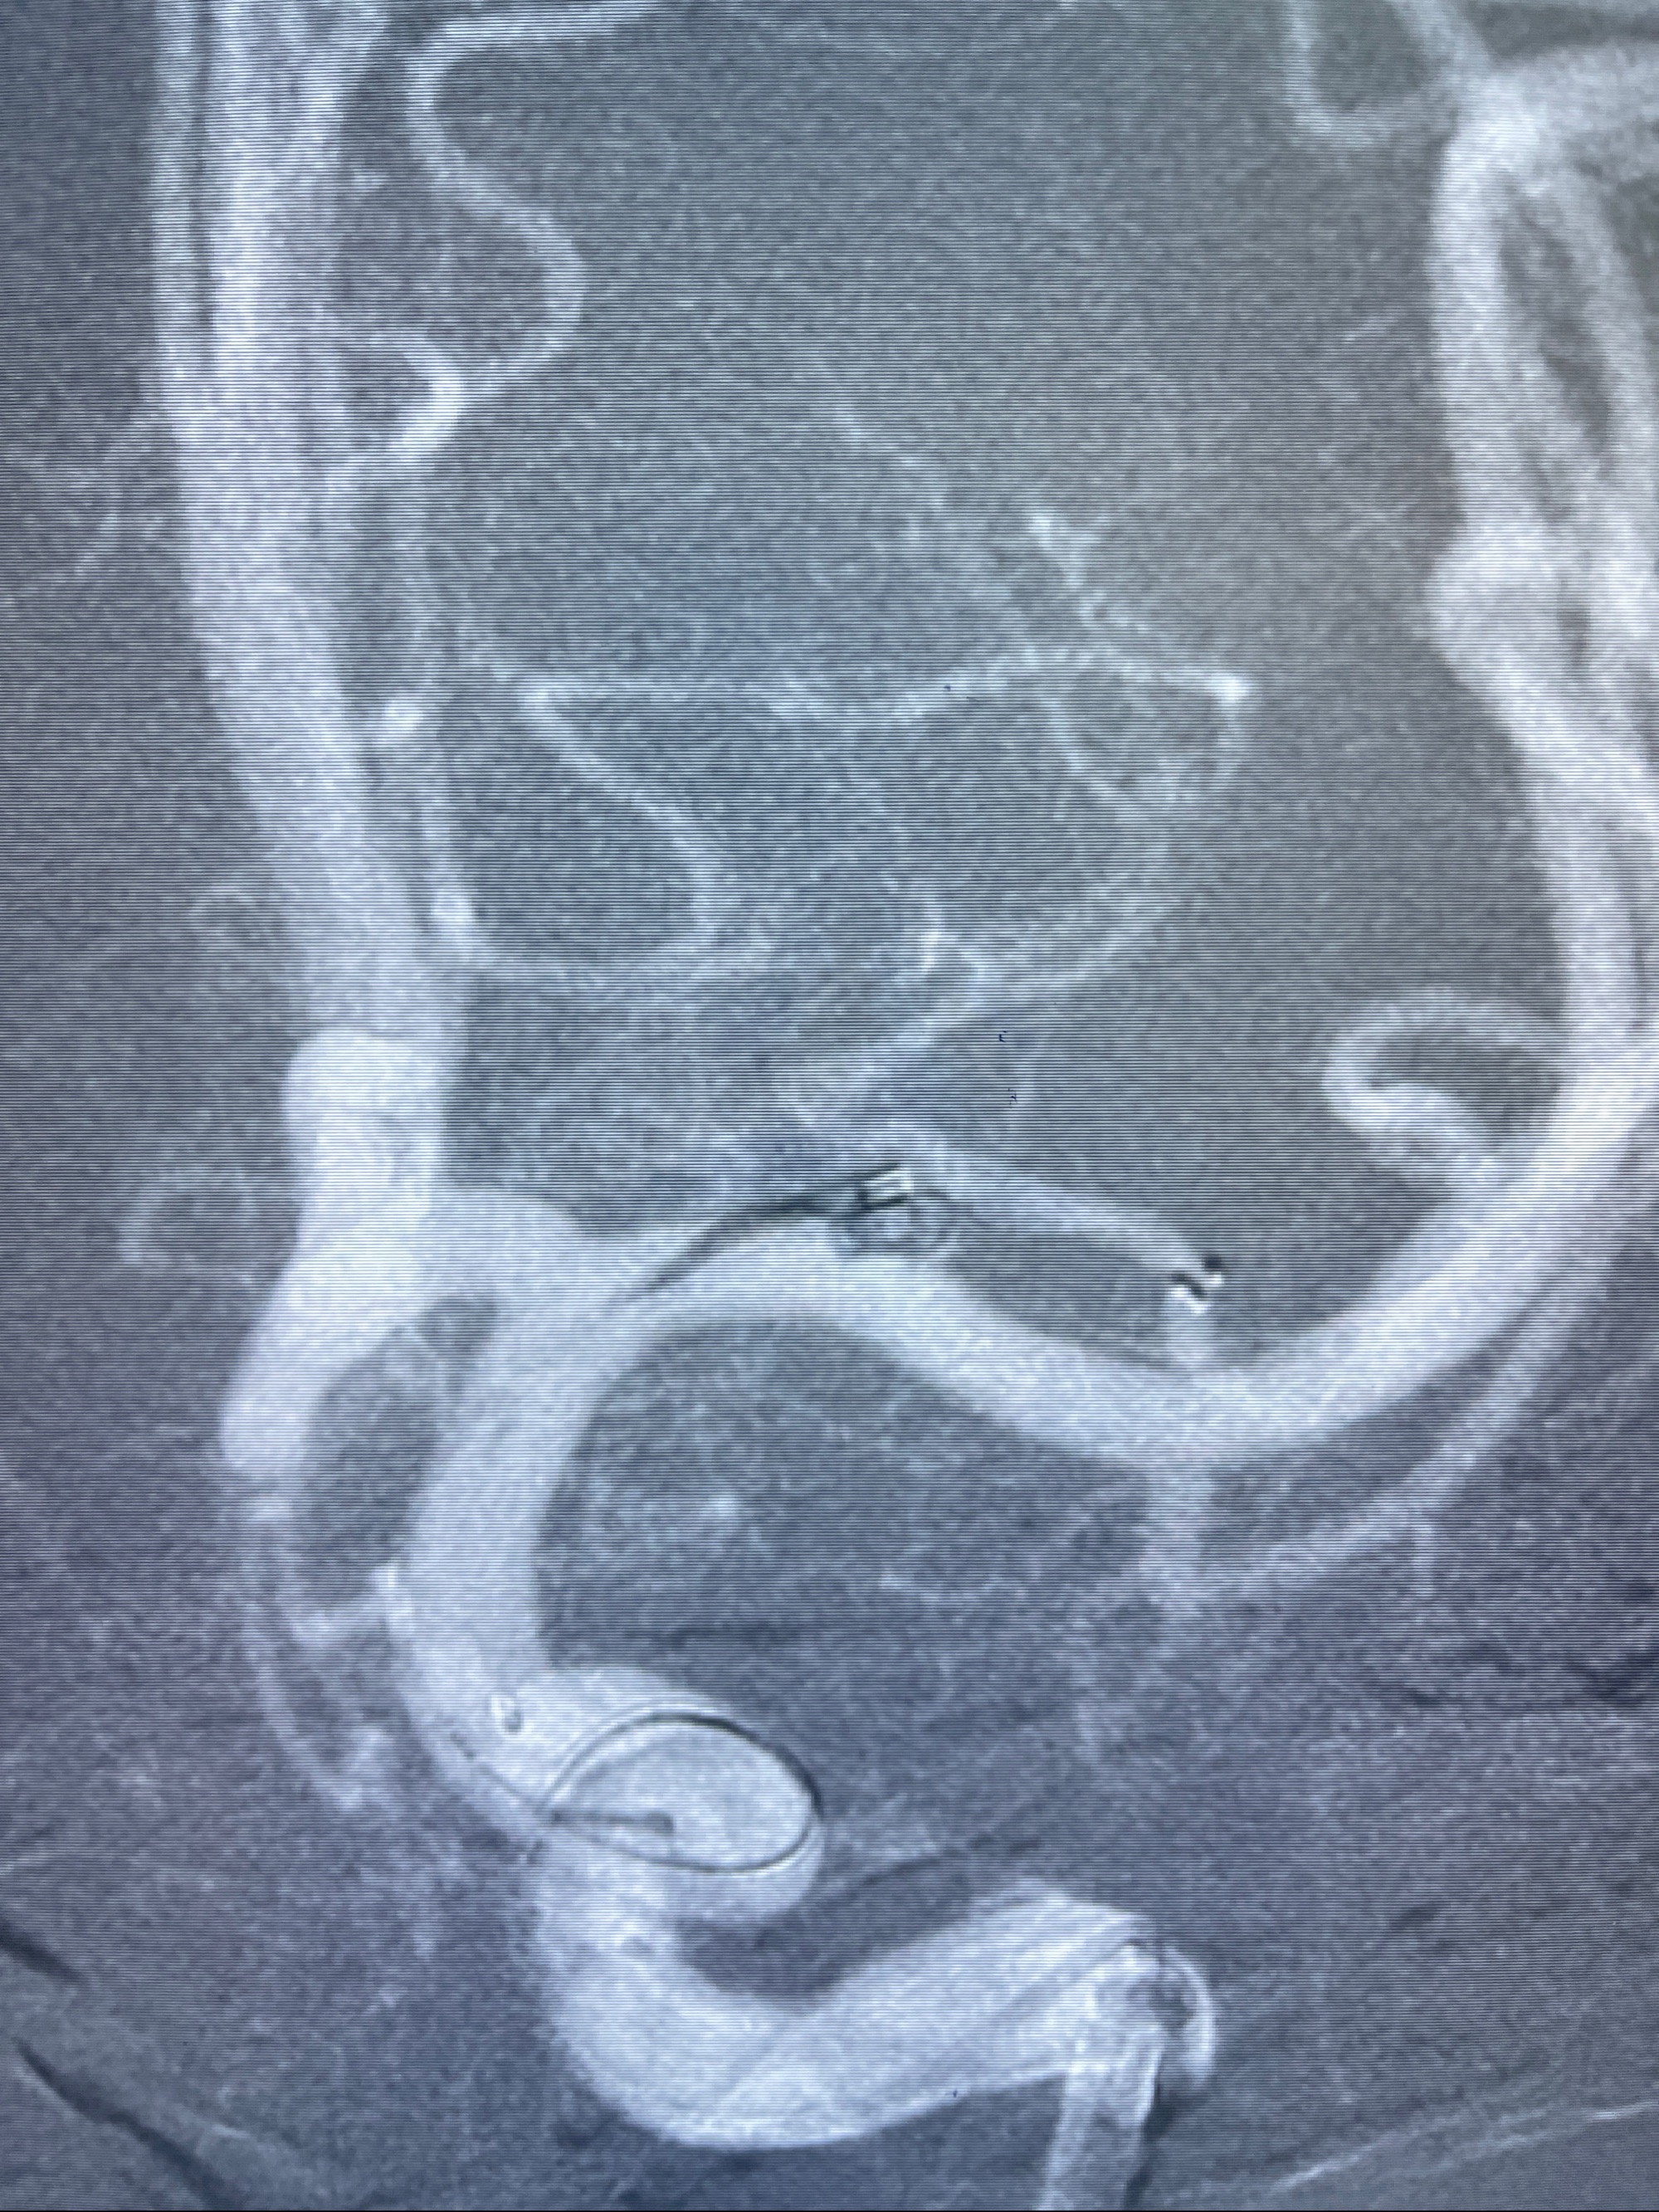

2023-08-14DSA:

左侧大脑中动脉动脉瘤,约2.6-2.8-3.4-2mm大小(瘤颈部、瘤体部、瘤高)

2.外科手术夹闭or介入支架辅助栓塞